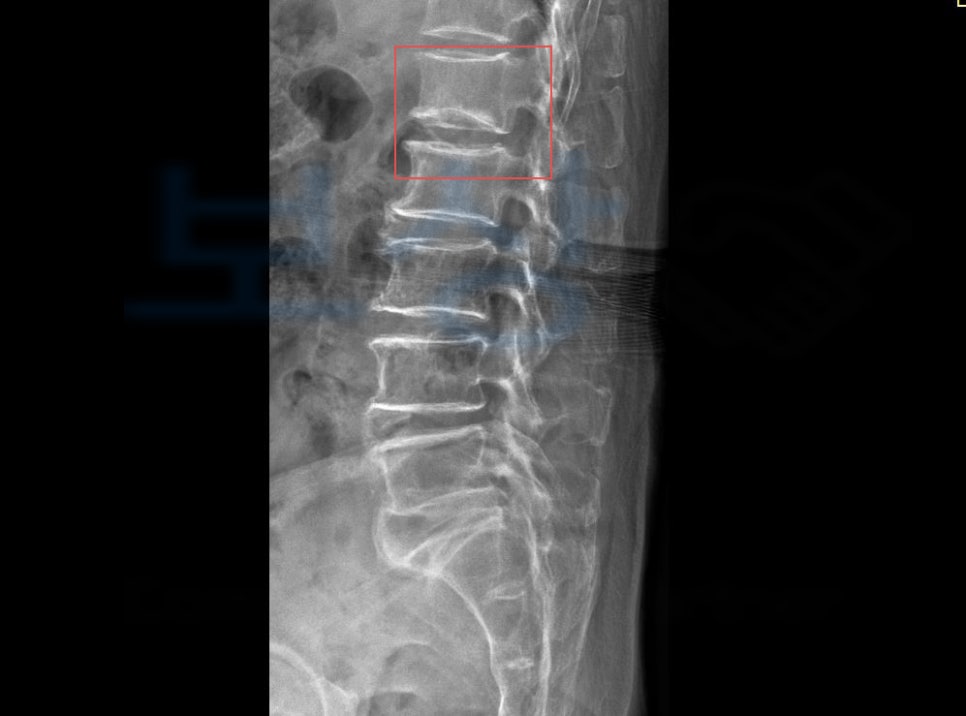

위 사고로 이@@님은 극심한 허리 통증을 호소했고 정밀 검사 상 나온 진단명은

L1 부위의 골절 s32020

경추 염좌, 요추 염좌 진단을 받으셨습니다.

**척추에 경미한 장해 15%**에 해당하셨습니다. 저희는 위 진단서를 기초로 손해사정서 및 관련 증빙서류를 검토 및 준비하여 보험사에 청구하였습니다. 물론 보험사에서는 심사를 진행하여 내부자문, 의료자문등을 거쳐 약 2달간의 분쟁이 오갔지만, 결국!